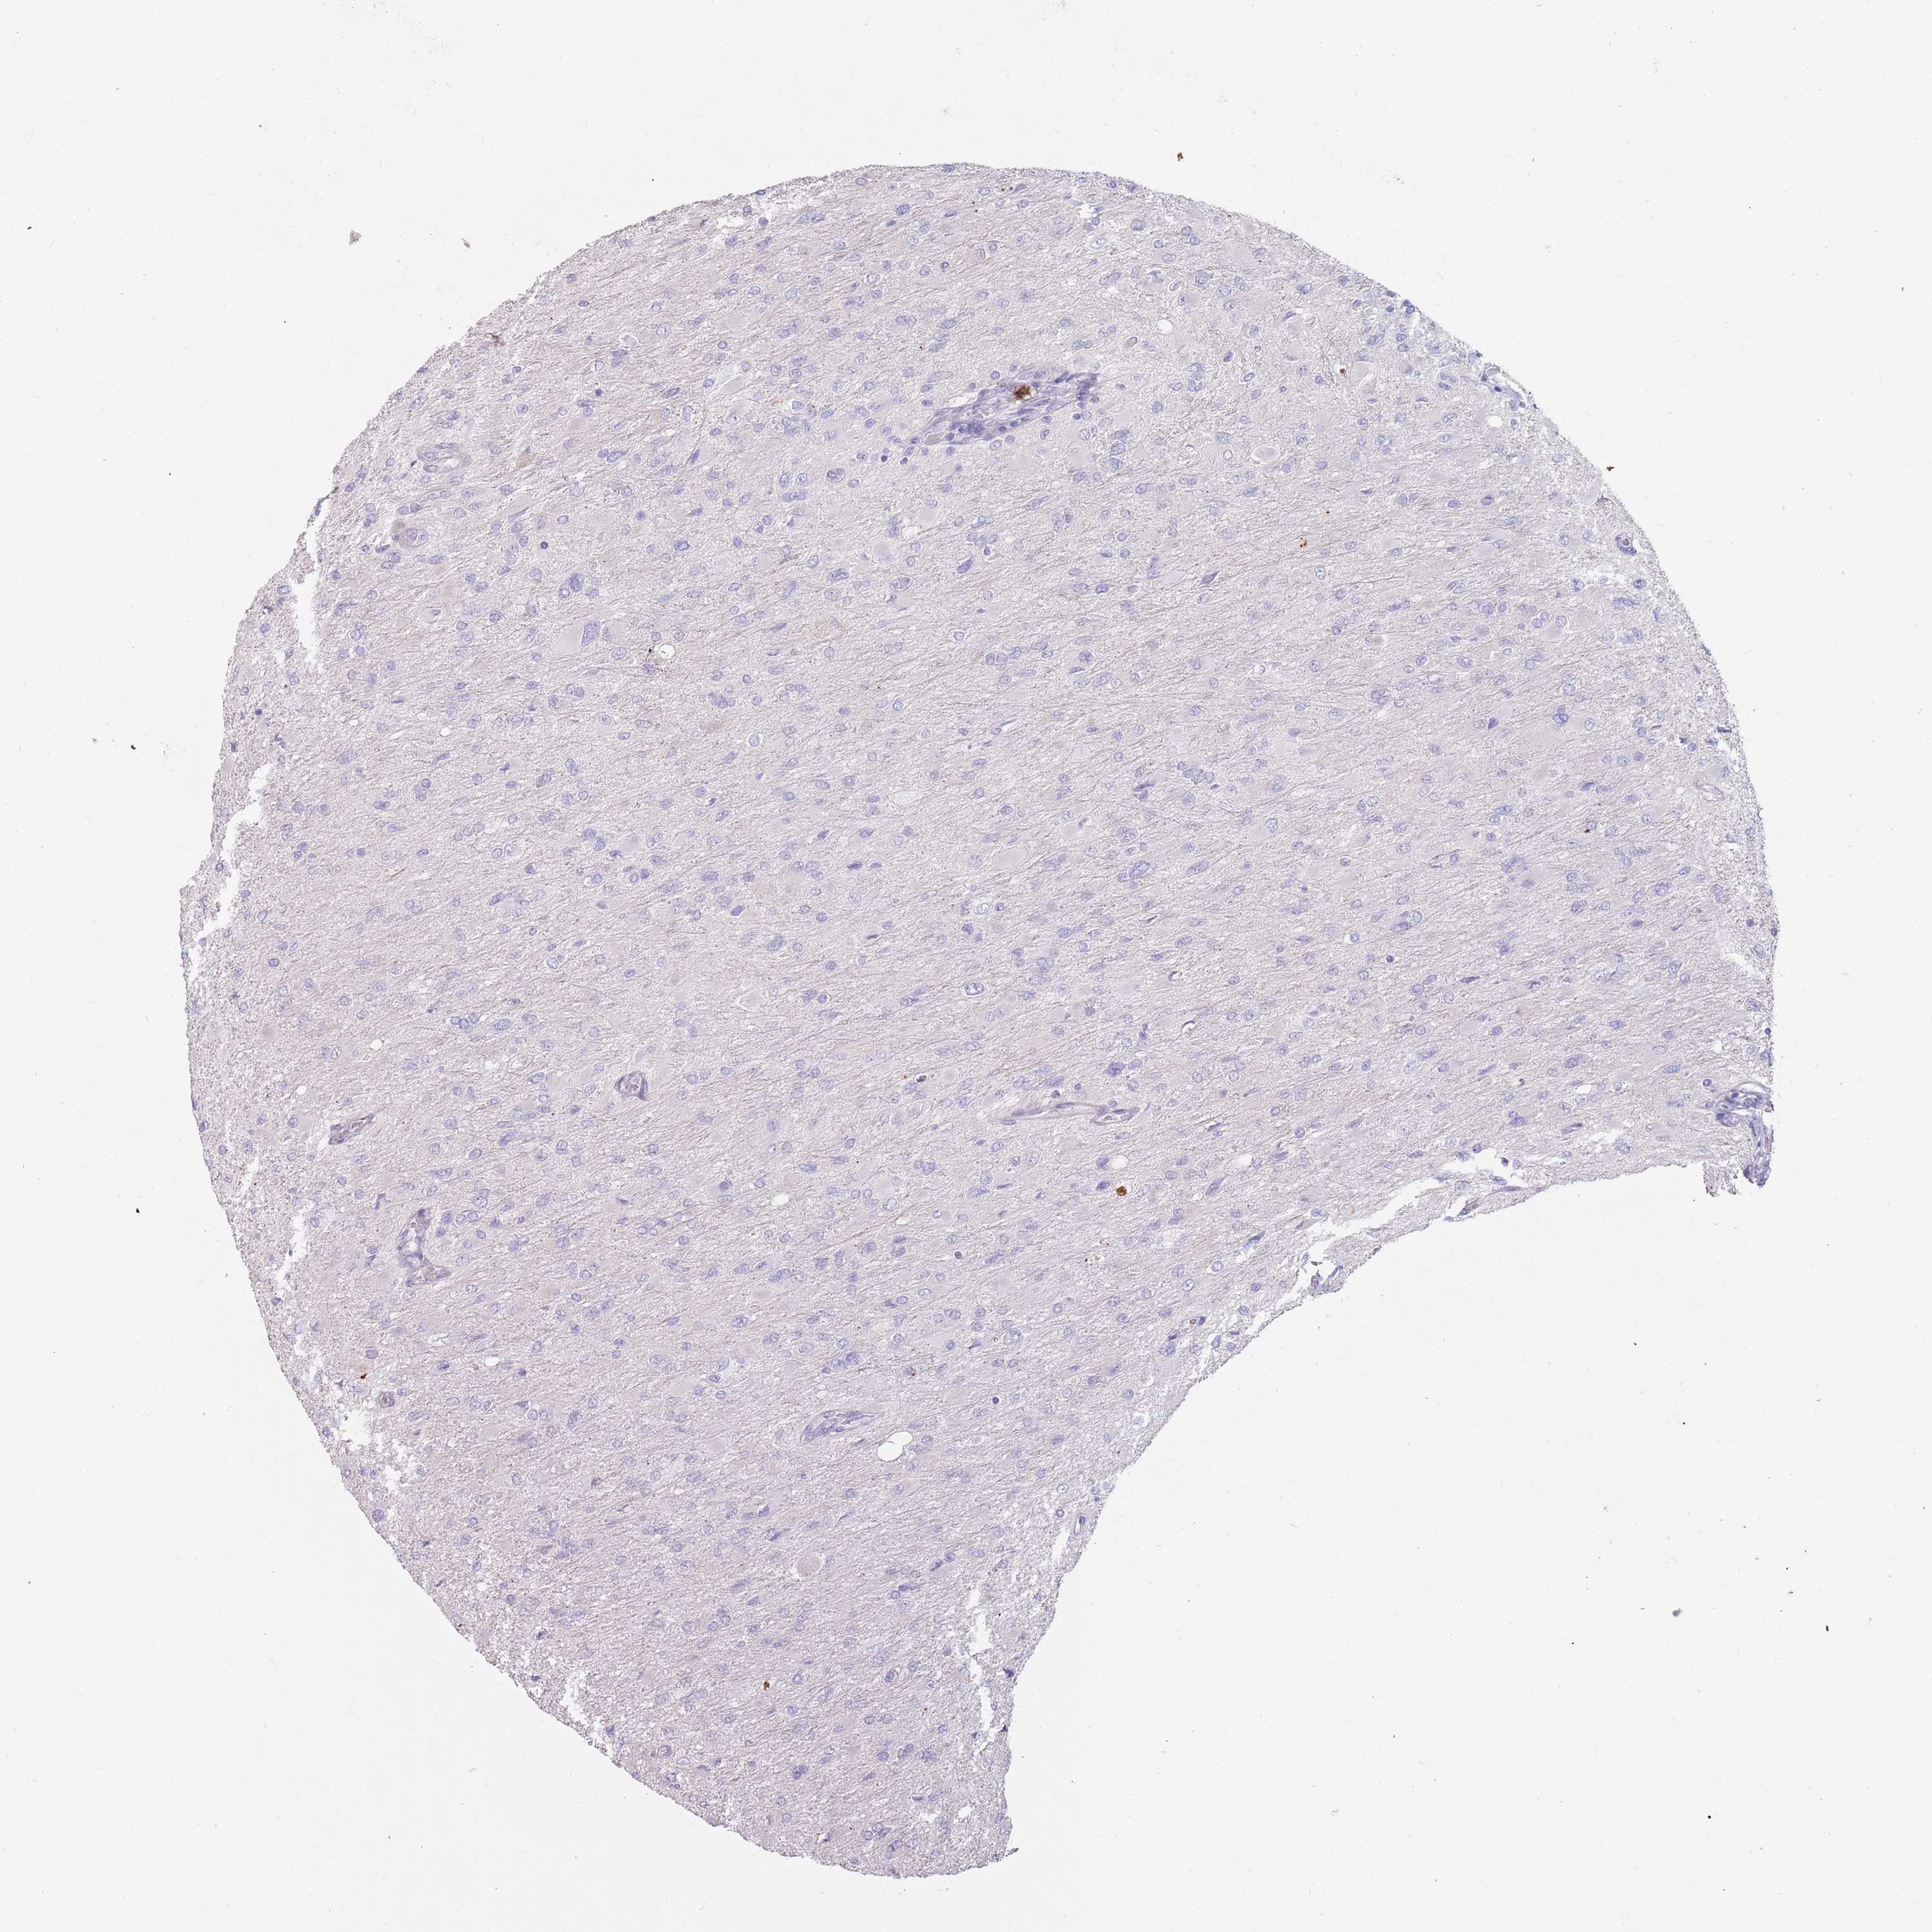

GLIOMA - Protein expressioni

A mouse-over function shows sample information and annotation data. Click on an image to view it in a full screen mode. Samples can be filtered based on level of antibody staining by selecting one or several of the following categories: high, medium, low and not detected. The assay and annotation is described here.

Note that samples used for immunohistochemistry by the Human Protein Atlas do not correspond to samples in the TCGA dataset.

Antibody stainingi

Antibody staining in the annotated cell types in the current human tissue is reported as not detected, low, medium, or high, based on conventional immunohistochemistry profiling in selected tissues. This score is based on the combination of the staining intensity and fraction of stained cells.

Each image is clickable and will lead to virtual microscopy that enables deeper exploration of all samples and also displays staining intensity scores, fraction scores and subcellular localization as well as patient and tissue information for each sample.

Antibody HPA046708

Staining

High

Medium

Low

Not detected

Intensity

Strong

Moderate

Weak

Negative

Quantity

>75%

75%-25%

<25%

None

Location

Nuclear

Cytoplasmic/membranous

Cytoplasmic/membranous,nuclear

Glioma, malignant, High grade

Glioma, malignant, Low grade